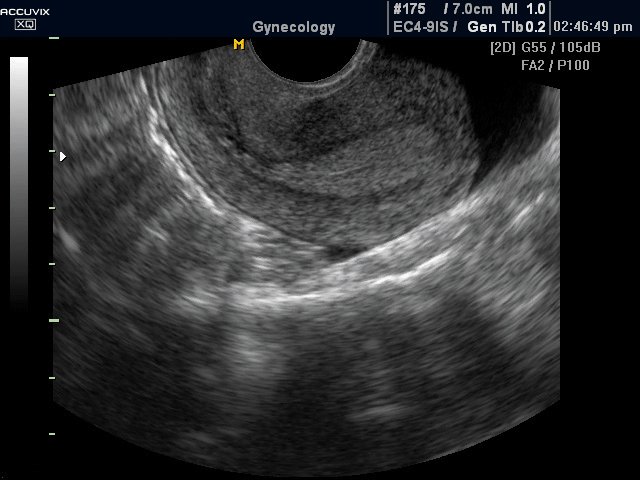

Медицинская диагностика: Гиперплазия эндометрия на УЗИ